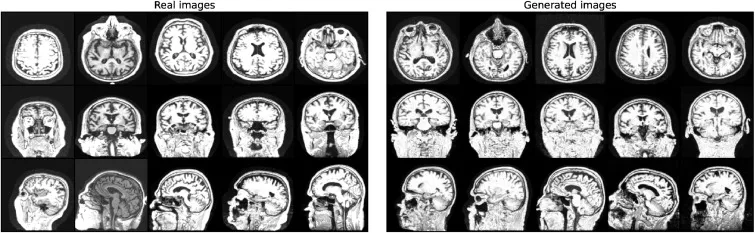

本研究首先通过定性(图2)和定量(表1、表2)分析评估了合成MRI图像的质量。结果显示,合成图像具有高真实感,且记忆化问题不明显,最高相关性(0.79)甚至低于AIBL与真实ADNI数据集之间的相关性(0.8)。在AD诊断任务中,在3T ADNI数据集上,基于合成数据预训练的2D ADnet模型在CN/AD二分类任务中取得了91.3%的准确率,优于基线模型28.8个百分点,并比最先进方法高8.8个百分点。在CN/MCI/AD三分类任务中,2D ADnet达到了74.5%的准确率和74.2%的F1分数,同样显著优于基线模型和ImageNet预训练模型。值得注意的是,使用合成数据预训练的模型性能与使用真实数据预训练的“Oracle”模型(数据量是合成数据的四倍)仅有0.3个百分点的差距。在OASIS-2数据集的ND/C/D分类任务中,我们的最佳模型达到了59.3%的准确率和57.6%的F1分数,超越了所有竞争模型。消融研究进一步表明,合成数据预训练在不同数据集大小下均能保持稳定的高性能,并且始终优于使用真实数据进行的预训练;同时,预训练的模型在不同微调数据集大小下都表现出更高的鲁棒性,并持续优于从零开始训练的模型。

图2.真实(左)和生成(右)的MRI切片在三个解剖视图中的比较:轴位(顶部)、冠状位(中部)和矢状位(底部)。